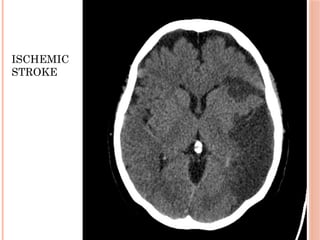

CT SCAN

 Infarct appears as a hypodense area

SAH

ISCHEMIC

STROKE